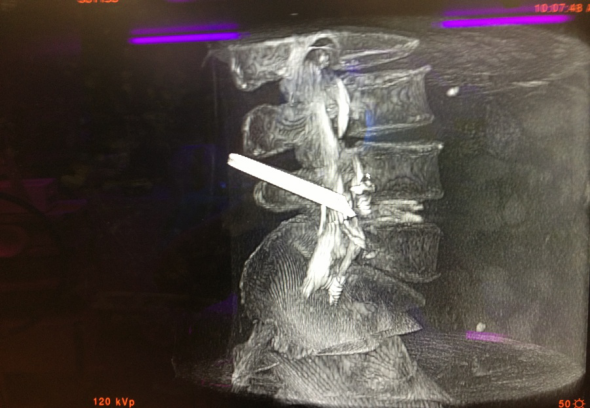

(5)O型臂多维外科成像系统证实通道建立良好(图9)。

图9 三维立体成像显示工作通道